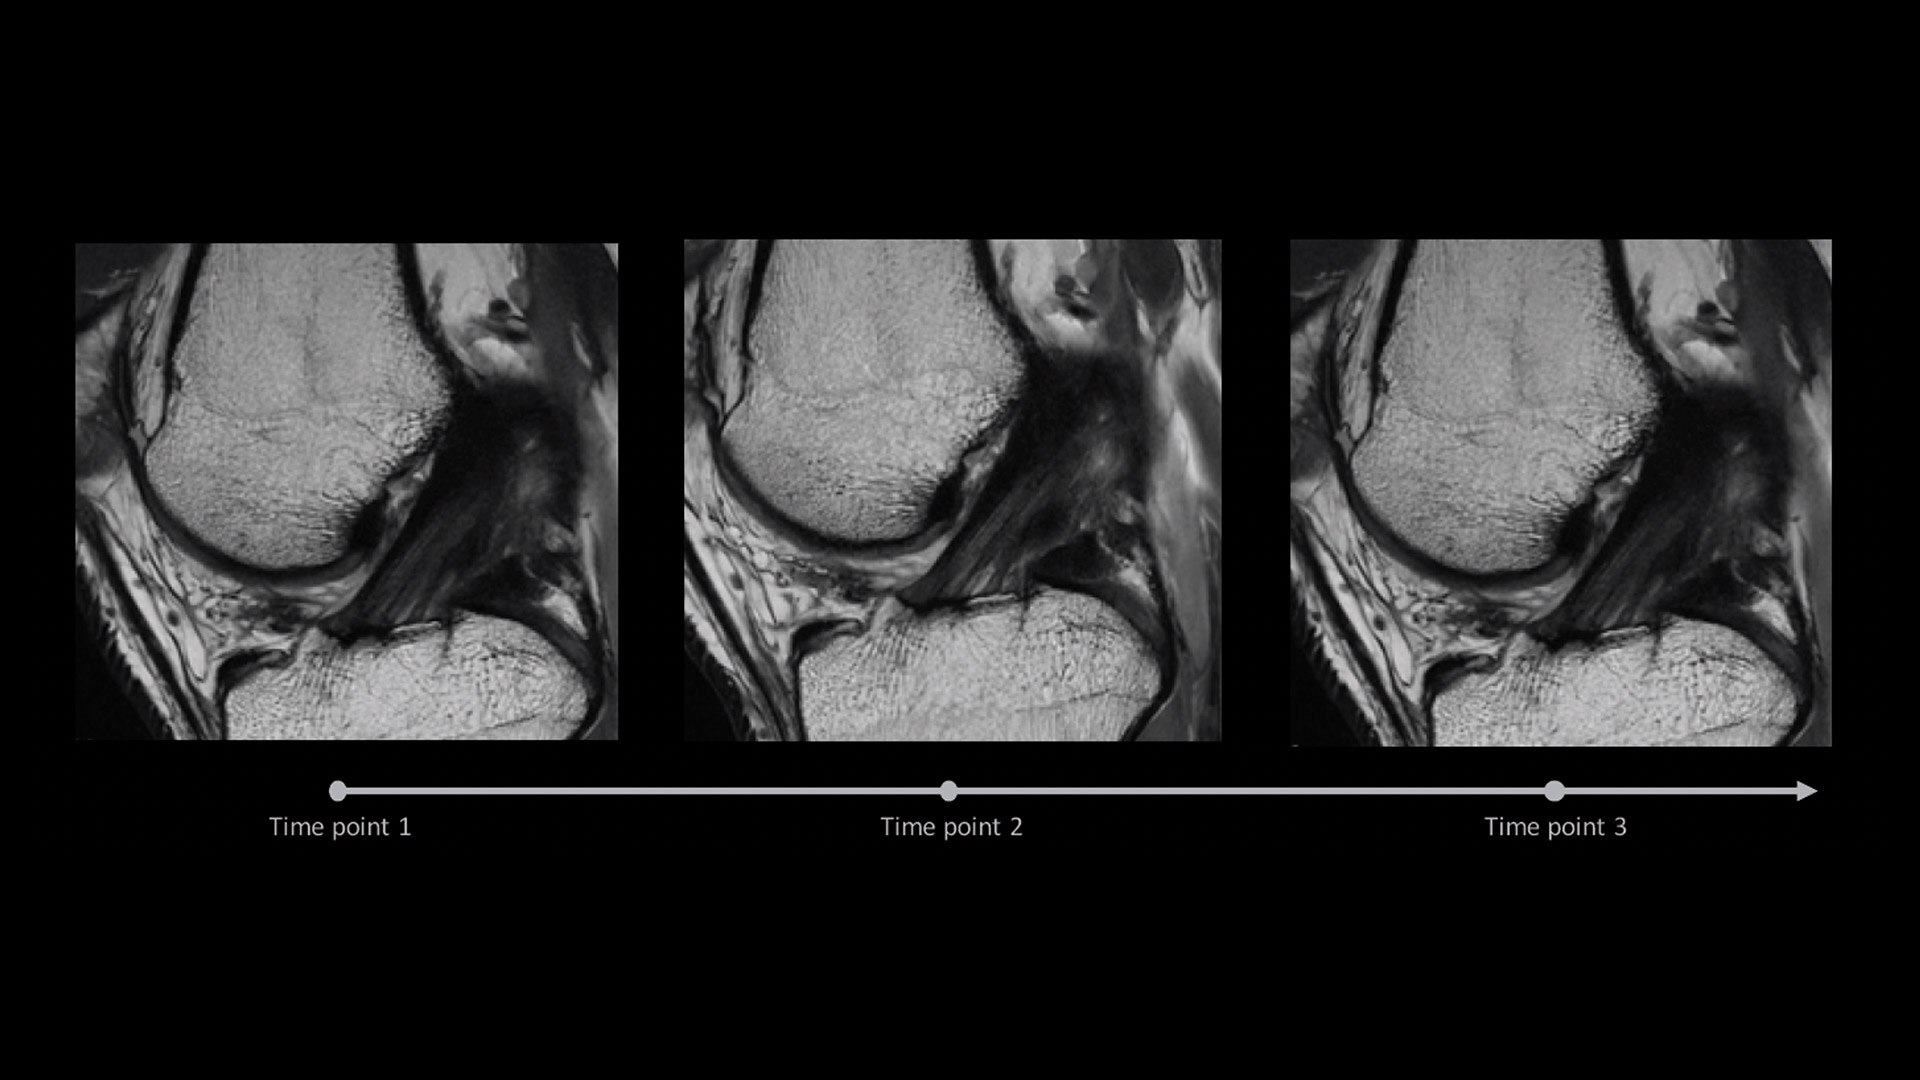

Eliminate the sources of variation by letting processes flow. AIR x™ uses deep-learning algorithms created from a database of 10's of thousands of images to automatically detect patient anatomy and prescribe MRI slices for routine and challenging neurological and knee exams, delivering consistent and quantifiable results. The automated workflow creates efficiency and reproduces steps used in planning to ensure exam consistency for same patient follow-up.

AIR x™ automatically detects patient anatomy and prescribes MRI slices for routine and challenging neurological and knee exams, delivering consistent and quantifiable results.

Deliver consistent MRI slice placements across multiple clinical time points, with a deep-learning algorithm that provides efficiency and time savings.